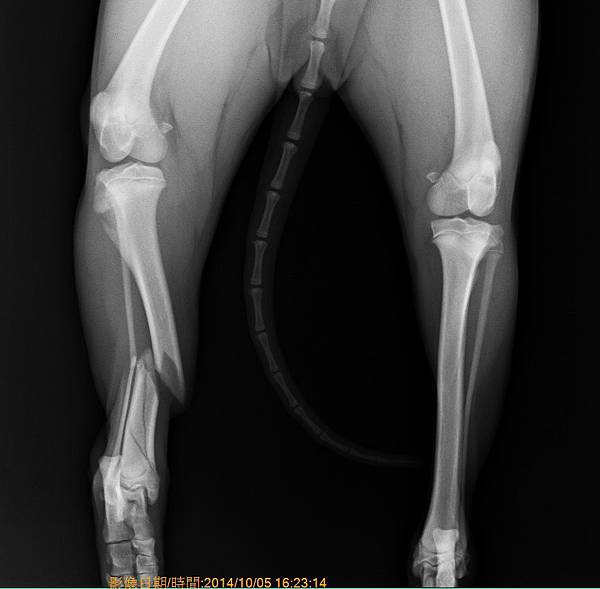

上圖為手術前X光: 小腿骨折的很誇張

1.jpg

2.jpg